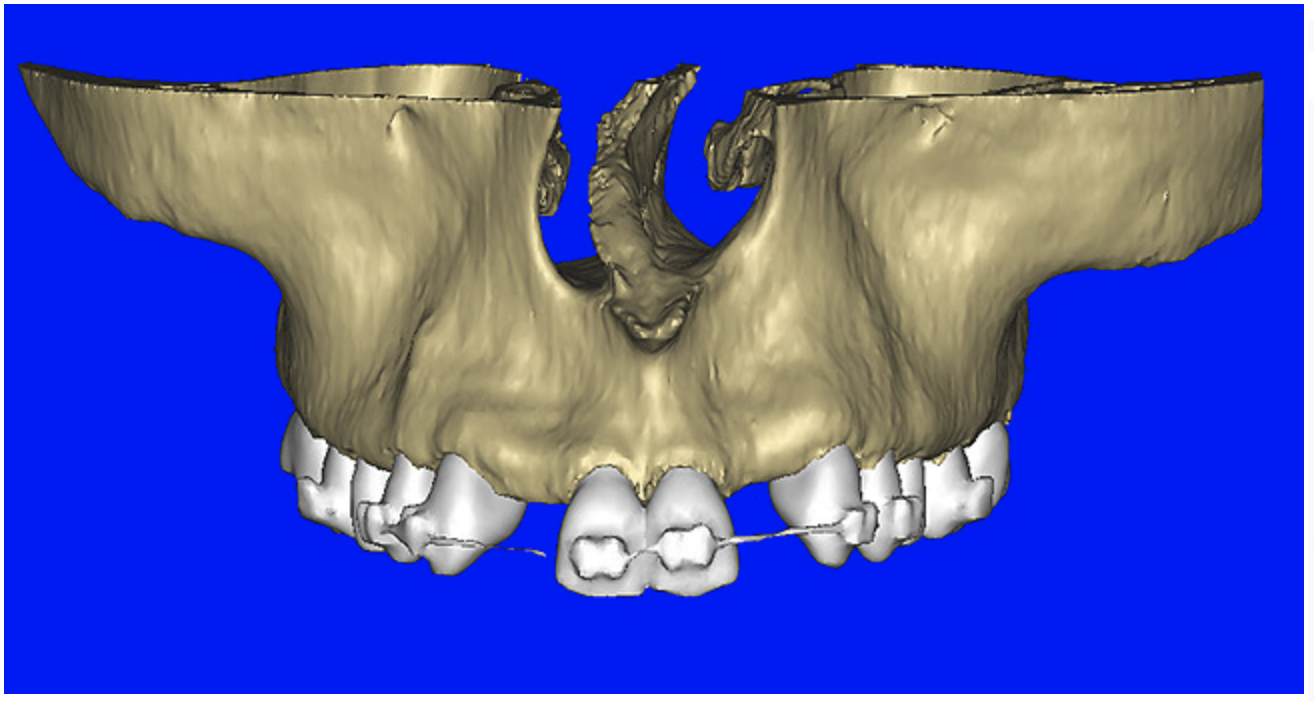

After the basic plan had been established, it was re-evaluated using interactive 3D images. The reconstructed 3D view of the maxilla clearly illustrated the extent of the bilateral facial concavities, and the root eminences of the adjacent and posterior teeth (Figure 7A). The placement of the virtual implants then was evaluated to ensure that the facial cortical plate was not perforated (Figure 7B). The implants were labeled individually as “7” and “10,” with the simulated yellow abutment projection indicating the facial-lingual inclination through the bone to the level above the incisal edge of adjacent teeth. The ability to gain a better understanding of these individual root forms can not be underestimated. The dental literature has suggested certain parameters for placing implants near teeth and implants next to other implants. However, there is little scientific 3D documentation to support these suggested rules.5-10 The use of an interactive treatment-planning software application permits closer scrutiny of previously difficult-to-visualize areas, and can now be used to redefine perceptions of spatial positioning of implants, especially when in close proximity to natural tooth roots, vital anatomy, and adjacent implants.27-29

Figure 7a  The 3D reconstruction showed (A) the facial concavities and root eminences, and allowed (B) for evaluation of virtual implant placement to ensure the facial cortical plate was not perforated.

Figure 7a

Figure 7b  The 3D reconstruction showed (A) the facial concavities and root eminences, and allowed (B) for evaluation of virtual implant placement to ensure the facial cortical plate was not perforated.

Figure 7b